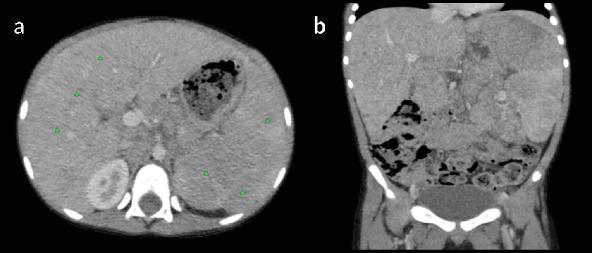

T-cell/histiocyte-rich large B-cell lymphoma (THRLBCL) is a rare and aggressive subtype of diffuse large B-cell lymphoma (DLBCL) that is uncommon in children. Here, we present the case of an 8-year-old male with a 3-month history of low-grade intermittent fever, significant weight loss, loss of appetite, and progressive abdominal swelling. Examination revealed splenomegaly and a palpable midabdominal mass, with laboratory findings showing bicytopenia. Imaging demonstrated hepatosplenomegaly, diffuse hypodense liver and spleen lesions, and mesenteric and retroperitoneal lymphadenopathy. A core-needle biopsy of the mesenteric mass confirmed the diagnosis, with histopathology revealing scattered large mononuclear and binucleate cells in a background of small lymphocytes and histiocytes. Immunohistochemistry showed positivity for CD45, CD20, and EMA and negativity for CD30, CD15, and Bcl-2, excluding alternative diagnoses such as nodular lymphocyte-predominant Hodgkin lymphoma (NLPHL) and classical Hodgkin lymphoma (cHL). The patient was initially stabilized with a prephase regimen of cyclophosphamide, vincristine, and prednisone (COP), followed by induction and consolidation with R-COPADM (rituximab, cyclophosphamide, vincristine, prednisone, and methotrexate). Posttreatment imaging revealed significant resolution of lymphadenopathy and hepatosplenomegaly, with no residual or recurrent disease. At follow-up, the patient remains in clinical remission with no signs of progression. This case highlights the importance of early recognition, detailed histopathological evaluation, and the role of immunohistochemistry in accurately diagnosing THRLBCL in children, ensuring timely initiation of effective therapy and improving outcomes in this rare pediatric malignancy.

富于T细胞/组织细胞的大B细胞淋巴瘤(THRLBCL)是弥漫性大B细胞淋巴瘤(DLBCL)中一种罕见且侵袭性的亚型,在儿童中并不常见。在此,我们报告一例8岁男性患儿,有3个月的低热间歇性发热、显著体重减轻、食欲不振及进行性腹部肿胀病史。检查发现脾肿大及可触及的中腹部肿块,实验室检查结果显示全血细胞减少。影像学检查显示肝脾肿大、肝脏和脾脏弥漫性低密度病变以及肠系膜和腹膜后淋巴结肿大。肠系膜肿块的粗针活检确诊了诊断,组织病理学显示在小淋巴细胞和组织细胞背景中有散在的大单核细胞和双核细胞。免疫组化显示CD45、CD20和EMA阳性,CD30、CD15和Bcl-2阴性,排除了结节性淋巴细胞为主型霍奇金淋巴瘤(NLPHL)和经典型霍奇金淋巴瘤(cHL)等其他诊断。患者最初通过环磷酰胺、长春新碱和泼尼松(COP)的前期方案稳定病情,随后用R-COPADM(利妥昔单抗、环磷酰胺、长春新碱、泼尼松和甲氨蝶呤)进行诱导和巩固治疗。治疗后的影像学检查显示淋巴结肿大和肝脾肿大明显消退,无残留或复发病变。随访时,患者仍处于临床缓解期,无进展迹象。该病例强调了早期识别、详细的组织病理学评估以及免疫组化在准确诊断儿童THRLBCL中的重要性,确保及时开始有效的治疗并改善这种罕见儿童恶性肿瘤的预后。